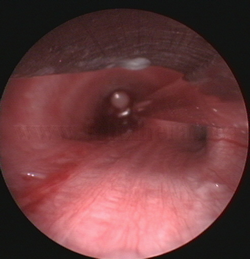

Cuerpo

extraño endobronquial |